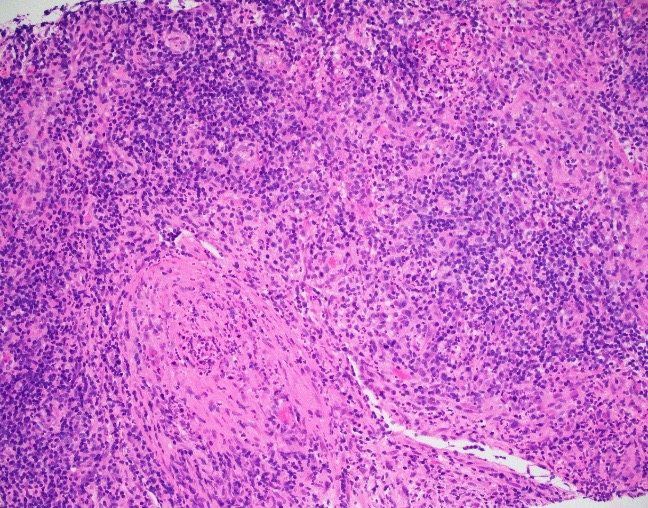

Abdominal ultrasonography demonstrated hepatosplenomegaly with enlarged porta-hepatis lymph nodes. Additionally, chest CT scanning demonstrated bilateral mass-like consolidations, prominent hilar lymphadenopathy, and osteolytic lesions of the vertebral bodies. A comprehensive investigation for opportunistic infections was negative. Lung and vertebral body biopsies (not pictured here) revealed poorly formed granulomas. A blood transfusion was considered; however, the patient had previously been demonstrated to express anti-Kx antibodies, which would require transfusion with exceedingly rare blood products.

The McLeod phenotype is frequently associated with CGD due to the proximity of the XK gene to the CYBB gene on the X chromosome. The CYBB gene encodes for a subunit of the NADPH oxidase enzyme complex. A deficiency in NADPH oxidase activity leads to the characteristic increased susceptibility to severe bacterial and fungal infections seen in CGD. The nitroblue-tetrazolium test can be used to evaluate NADPH oxidase activity in the white blood cells and can help make a diagnosis of CGD. Histologically, CGD can show prominent necrotizing and non-necrotizing granulomas in various locations throughout the body.